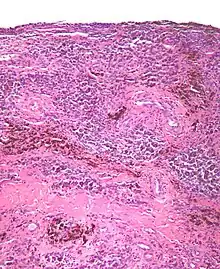

Micrograph of diffuse TGCT, also known as pigmented villonodular synovitis. H&E stain.

Micrograph of diffuse TGCT showing pigmented hemosiderin-laden macrophages (brown/red). H&E stain.